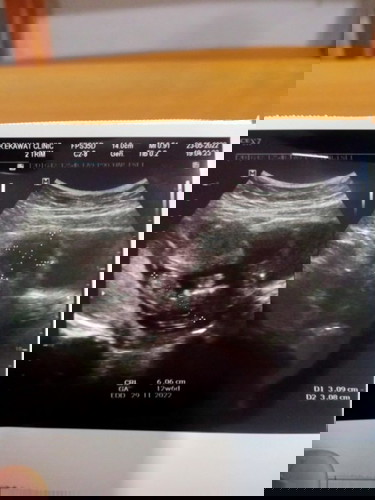

แม่กังวลใจค่ะคุณหมอทักว่าน้องตัวเล็กอายุครรภ์ 12wแม่ๆมีเคล็ดลับบำรุงลูกยังไงคะจากใบซาว 6.06 เซนค่ะ

น้องตัวใหญ่ดีนะคะแม่ 12w ขนาด6.06cm. บ้านนี้ 12wขนาดตัว 5.79cm. คะ หมอยังบอกแข็งแรงดี ดิ้นเก่งด้วยค่ะ ไม่ต้อวกังวลนะคะคุณแม่ กินของที่มีประโยชน์ ดีทั้งแม่และลูกจะดีมากคะ